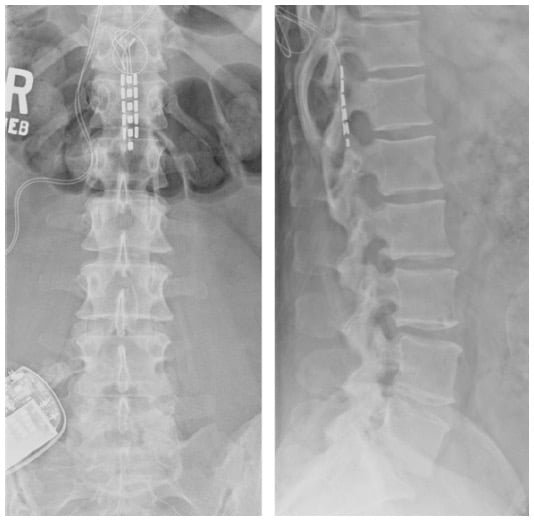

Intrathecal Baclofen Pump

Intrathecal Baclofen Pump is inserted by an experienced spine surgeon in Hyderabad and Secunderabad, India to treat severe spasticity. The pump can be filled with Baclofen (Spasticity) or Morphine (Pain). Indications of Baclofen Pump are:

- Cerebral palsy

- Spinal cord injury

- Head injury

- Multiple sclerosis

- Neurological Disorders